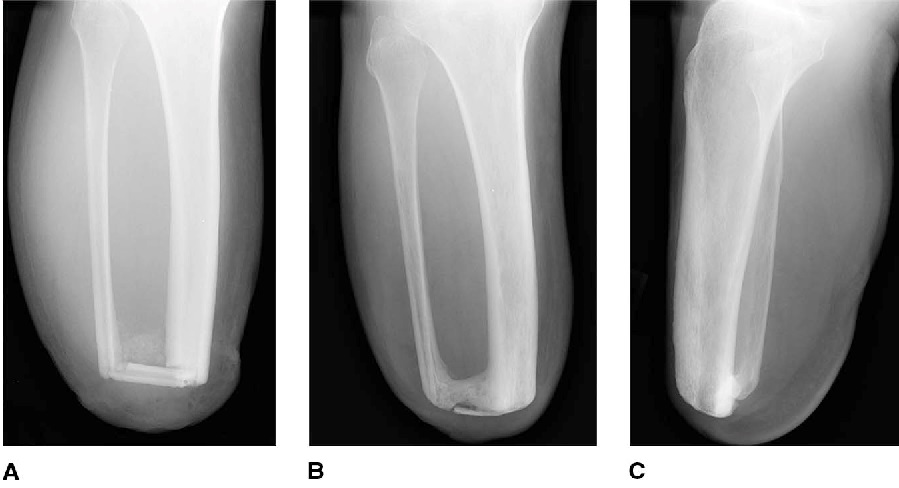

Anthony, what type of amputation did you have? Ertl, it is a below the knee operation where the surgeon takes a piece of bone and creates a bone bridge between the tibia and fibula.